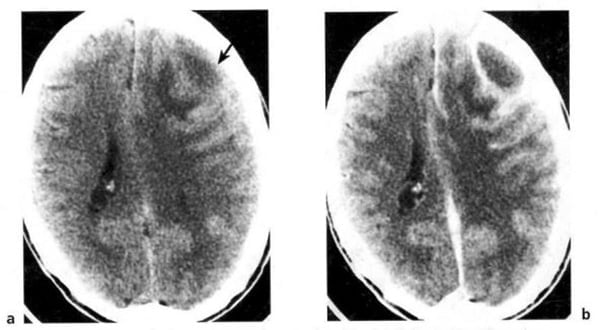

Hình 1.29. U tế bào hình sao độ 2. Ở vùng đỉnh thái dương sau bên trái (mũi tên). Bệnh nhân nam 40 tuổi. Trước tiêm, mật độ hai bên hơi bất xứng, mơ hồ (a). Sau tiêm, không thấy bắt chất cản quang (b). XQCLĐT thường âm tính. U hiện rõ trên CHT.